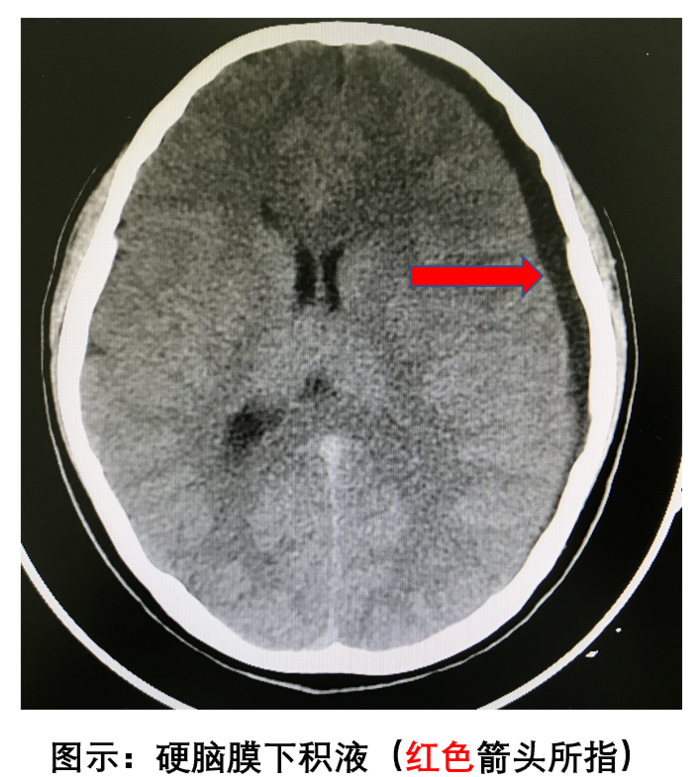

硬脑膜下积液